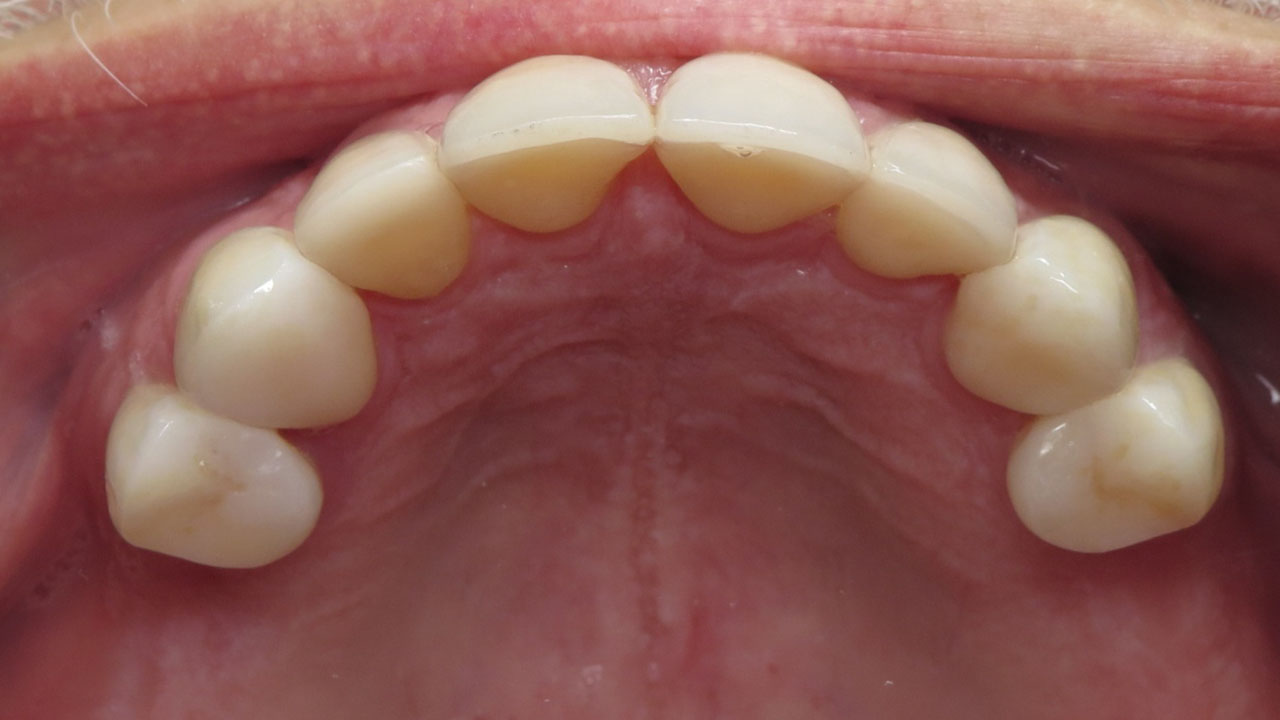

Hopeless lower teeth were removed and the remaining teeth were restored with all-ceramic crowns to rebuild the bite and protect the worn dentition.

Treatment was completed in stages. The upper teeth were restored first with all-ceramic crowns to rebuild the bite. After a pause to allow the patient time for physical and financial recovery, treatment continued with restoration of the lower teeth.

The result is a stable bite that protects the remaining teeth and restores comfortable chewing.